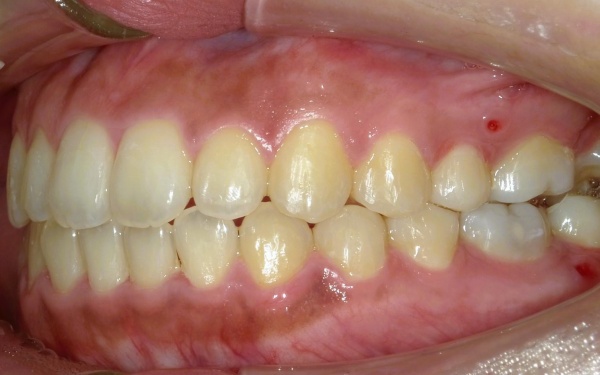

20代女性 重度のオープンバイトを小臼歯を抜歯しない非抜歯矯正かつ上顎前歯を挺出させずに(伸ばさずに)短期間で噛み合わせと口元の審美性を改善した症例

治療前

カウンセリング・診断結果 拝見したところ、上下の奥歯を噛み合わせた際、骨格的な要因によって前歯が噛み合わずに隙間ができる「開咬(かいこう)」、いわゆるオープンバイトが認められました。

患者様の場合、重度の開咬のため、前歯で物を噛み切ることが困難な状態です。

また、常に上下前歯の間に隙間があるため、発音に影響が出たり噛み合わせたときに奥歯への負担が増加したりすることで、将来的に歯や顎に痛みが生じるおそれがあります。